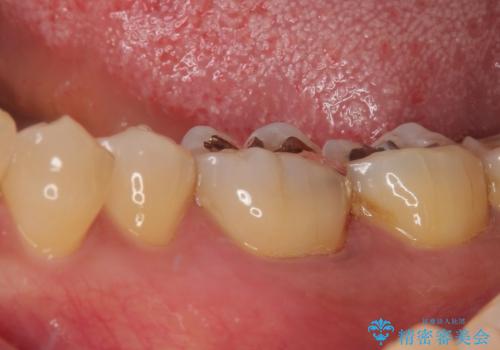

- 銀歯の周りに物が挟まるとのことで来院された患者様です。

咬合力が強く、銀歯周りの歯質に隙間が生じてむし歯になっている状態でした。

むし歯をしっかりと取り除き、強い咬合力を考慮してゴールドインレーにて修復することとしました。